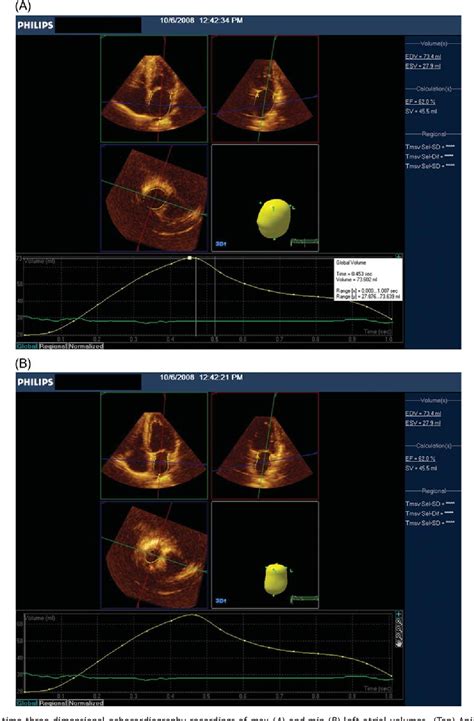

To put it simply, the heart is a muscular pump with four chambers. The lower chambers, known as the ventricles, are responsible for pumping blood out to the rest of the body. The Ejection Fraction Range specifically measures the volume of blood pumped out of the left ventricle—the heart’s main pumping chamber—with every heartbeat. It is expressed as a percentage. If your heart fills with 100 milliliters of blood and pumps out 60 milliliters, your ejection fraction is 60%. This number is a vital indicator used to diagnose, classify, and manage various heart conditions, particularly heart failure.

Medical experts generally categorize ejection fraction percentages to help determine the status of your cardiac health. While individual factors such as age, sex, and overall health status can influence these figures, the following table provides a general guideline for how clinicians interpret these percentages.

Ejection Fraction Category Percentage Range Clinical Interpretation

Normal 50% to 70% The heart is pumping efficiently.

Borderline 41% to 49% May indicate early signs of cardiac stress.

Reduced (Heart Failure) 40% or less Indicates HFrEF (Heart Failure with reduced EF).

Hyperdynamic Above 75% Can indicate certain conditions like hypertrophic cardiomyopathy.